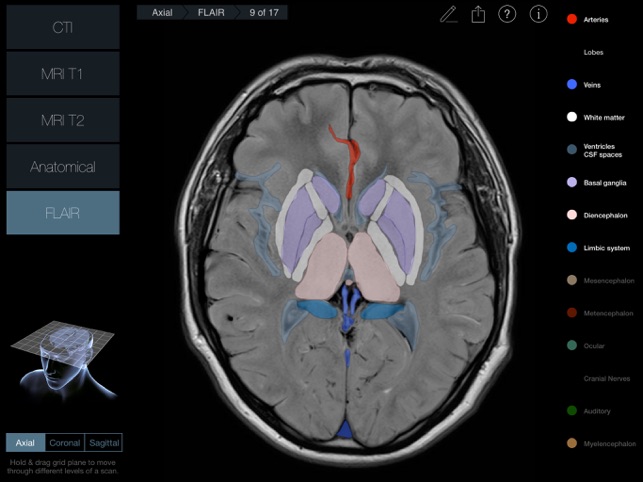

170 images in 3 planes with 2 scan types for each plane (a third for the Axial plane) and anatomical slices for each plane.

•MRI T1 (Spin-Echo T1-weighted Magnetic Resonance Imaging)

•FLAIR – (Turbo Inversion Recovery-Magnitude Reconstruction)

A 3D plane (Axial, Coronal or Sagittal) is pulled or pushed through a 3D head to navigate through the 17 scans in that plane.

300 individual structures labeled along with descriptions and voice over pronunciations.

Individual structures are grouped into 14 categories and each category can be turned on or off to allow for clearer identification of structures.

Each scan and slice is anatomically identical, so every labeled structure is in the same position in every image and scan – this makes it much easier to identify variances in appearance of structures between scans.